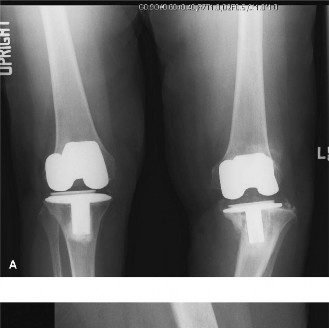

A 65-year-old female presents with a painful, left total knee replacement that was performed 7 years ago. The…